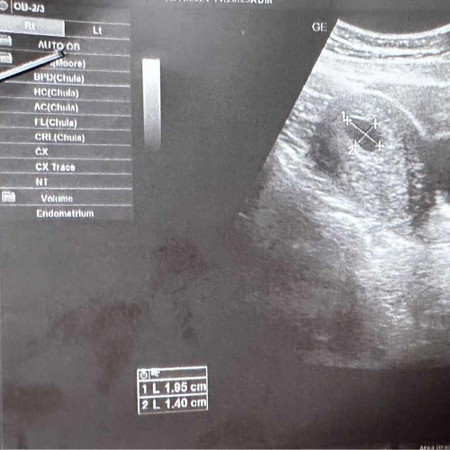

10w ไม่เจอตัวอ่อน

10wไม่เจอตัวอ่อน หมอสันนิษฐานว่าท้องลม มีแม่ๆบ้านไหนเจอน้องหลัง10wไหมคะ พอมีลุ้นไหมคะ😢

บ้านนี้ซาวตอน 10 วีคไม่เจอตัวน้องเหมือนกันค่ะ หมอนัดซาวอีกทีตอน 13 วีคไม่เจอน้องเหมือนเดิมหมอบอกท้องลมเสียใจมากค่ะทำใจไม่ได้😭😭 ขอให้คุณแม่เจอตัวน้องนะคะ

ของเรา10วีคเจอตัว แล้วก็ได้ยินเสียงหัวใจแล้วนะคะ